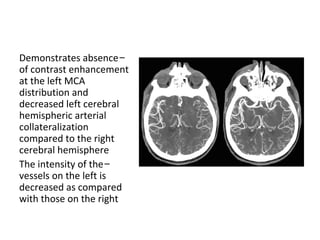

-Demonstrates absence

of contrast enhancement

at the left MCA

distribution and

decreased left cerebral

hemispheric arterial

collateralization

compared to the right

cerebral hemisphere

-The intensity of the

vessels on the left is

decreased as compared

with those on the right